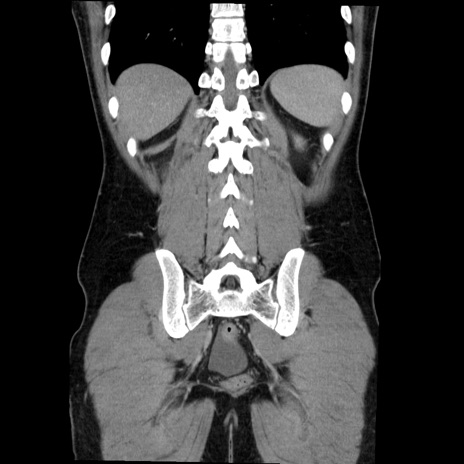

症例36(冠状断像)

【症例】20歳代 男性

【主訴】心窩部痛

【現病歴】今朝より上腹部痛あり。一旦軽快していたが再度出現したため救急要請。昨日夕に白身の魚を含む刺身を食べた。

【身体所見】BP 136/89mmHg、HR 74/min、BT 37.0℃、腹部:膨満、軟、心窩部に圧痛あり。反跳痛なし、筋性防御なし、腸雑音やや亢進あり。

【データ】WBC 17700、CRP 0.48